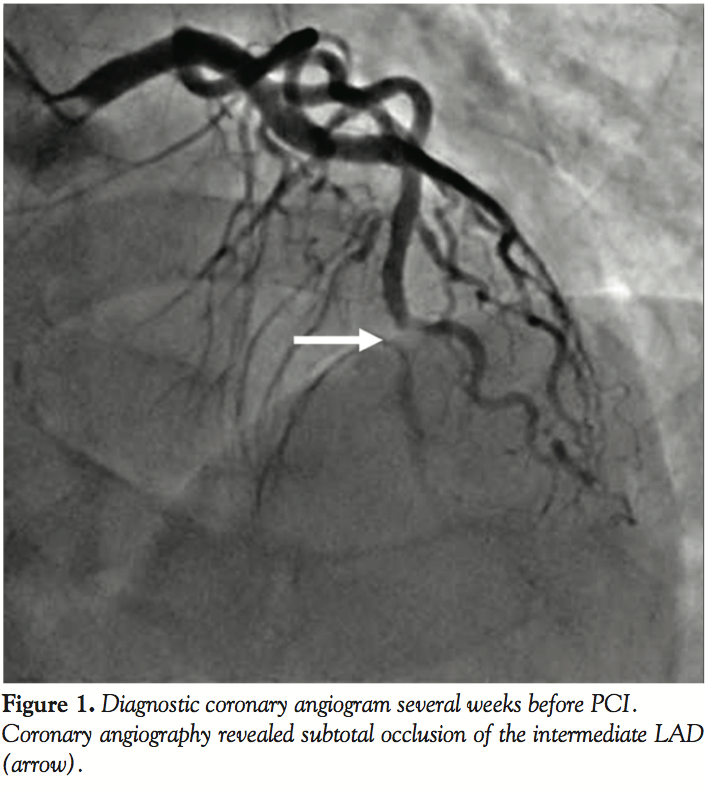

The patient was admitted and coronary angiography was performed on the following day after hydration with 0.9% saline at 1 ml/kg/hour. Subtotal occlusion of the intermediate left anterior descending artery (LAD) was observed (Figure 1). In total, 25 ml contrast medium was used. The blood test did not show further deterioration of the renal function.